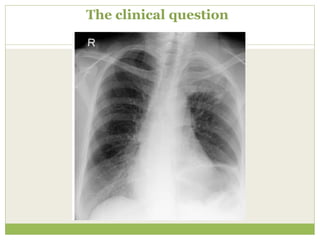

The clinical question

Clinical information provided

๏‚— Recent increase in shortness of breath

๏‚— No fever or productive cough

๏‚— Left shoulder and arm pain

๏‚— Heavy smoker

๏‚— Weight loss